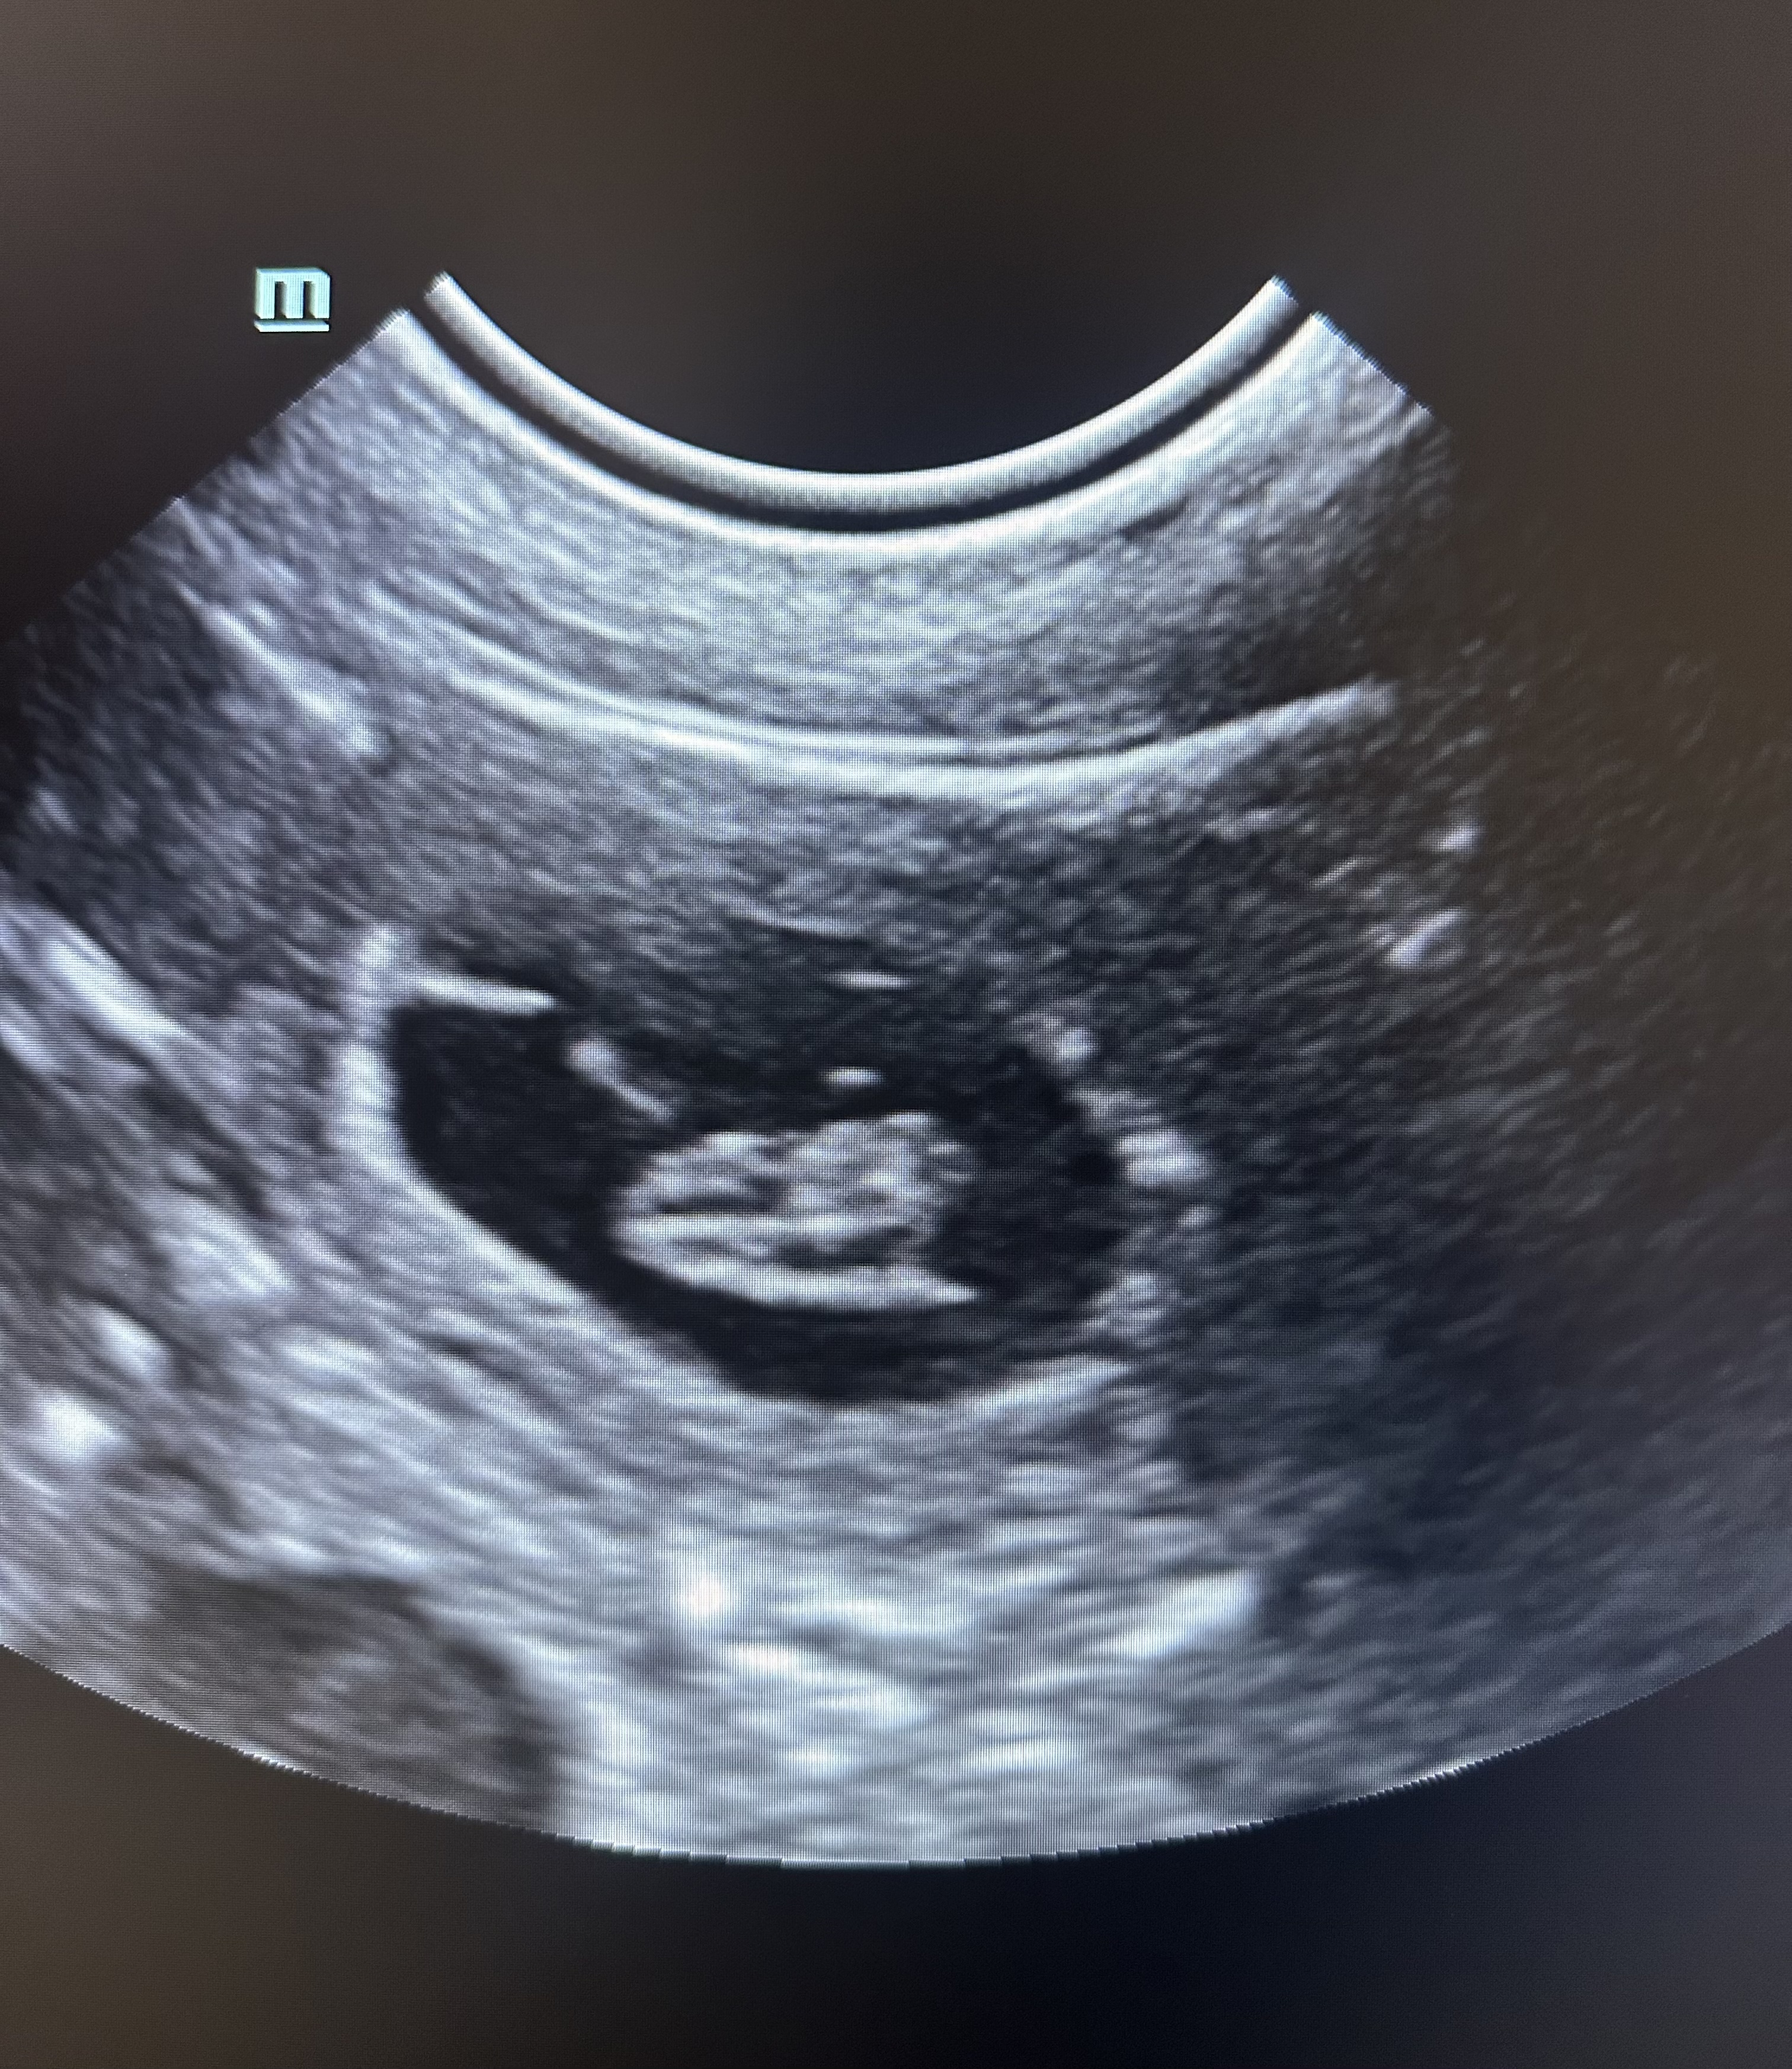

Abychom zjistili příčinu onemocnění, důležitou součástí je odběr krve a její vyšetření v NAŠÍ laboratoři. Pokud je nutné provádíme sonografické a/nebo rentgenologické vyšetření.